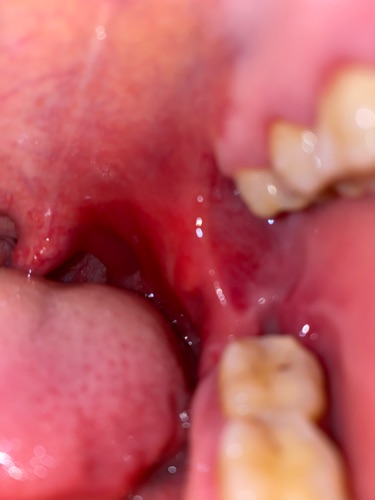

Chào bác sỹ . Tôi mới nhổ răng khôn đk 20 ngày . Bgiờ trong miệng tôi tự nhiên thấy đau . Có hiện tượng sưng đỏ . Mỗi lần nhuốt nước miếng và thức ăn là rất đau . Xin hỏi bác sĩ là tôi bị làm sao ạk ? Và có cách nào để khắc phục không ạk ? Mong bác sĩ rúp đỡ